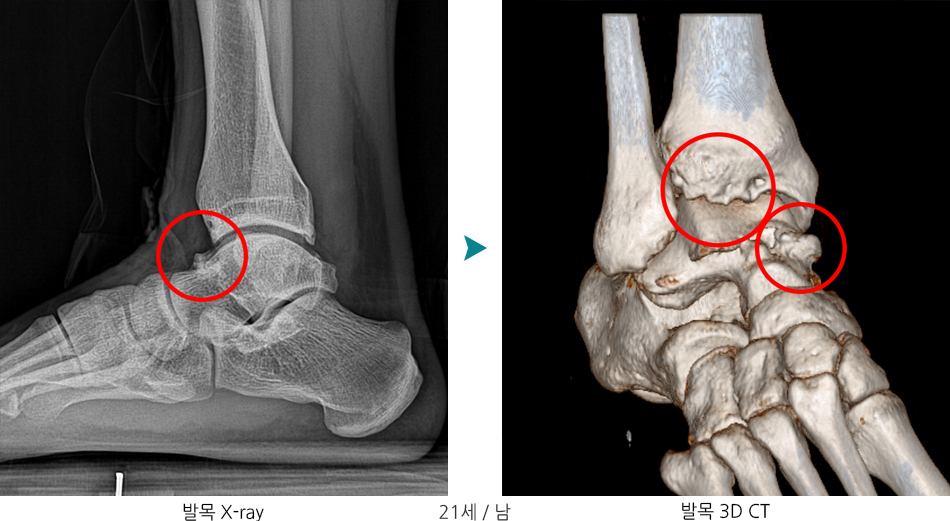

"발목 전방 충돌증후군 (Anterior Ankle Impingement)"

발목 앞쪽(전방)에서 뼈나 연부조직이 충돌하여 통증, 운동 제한을 유발하는 질환입니다. 보통 반복적인 염좌나 운동 중 미세 손상으로 인해 발목 앞쪽에 골극(뼈 돌기)이나 연부조직 비후가 생기면서 나타납니다.

- 관절 내 구조물의 비정상적 성장(골극 형성)

- 관절염 (퇴행성 변화로 인한 골극 형성)